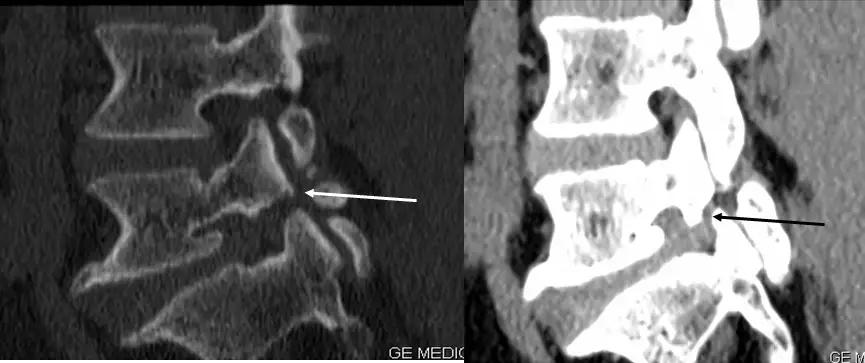

椎间盘突出的CT表现

直接征象:A、椎间盘后缘向椎管内局限性突出,密度与相应椎间盘一致,形态不一。B、突出的椎间盘可有大小、形态不一的钙化,多与椎间盘相连;C、椎管内硬膜外可见髓核游离碎片,密度高于硬膜囊;D、许莫结节表现为椎体上(下)缘边缘清楚的隐窝状压迹,多位于椎体中后1/3交界部,常上下对称出现。其中心密度低,为突出的髓核及软骨板,外周为反应性骨硬化带。

间接征象:A、硬膜外脂肪间隙变窄、移位、或消失。B、硬膜囊前缘或侧方及神经根受压移位。C、周围骨结构改变,突出髓核周围骨质硬化。

椎间盘突出示意图

正常椎间盘CT图像

椎间盘突出图像

椎间盘突出(中央型)

中央型

椎间盘突出右旁中央型

椎间盘突出左旁中央型